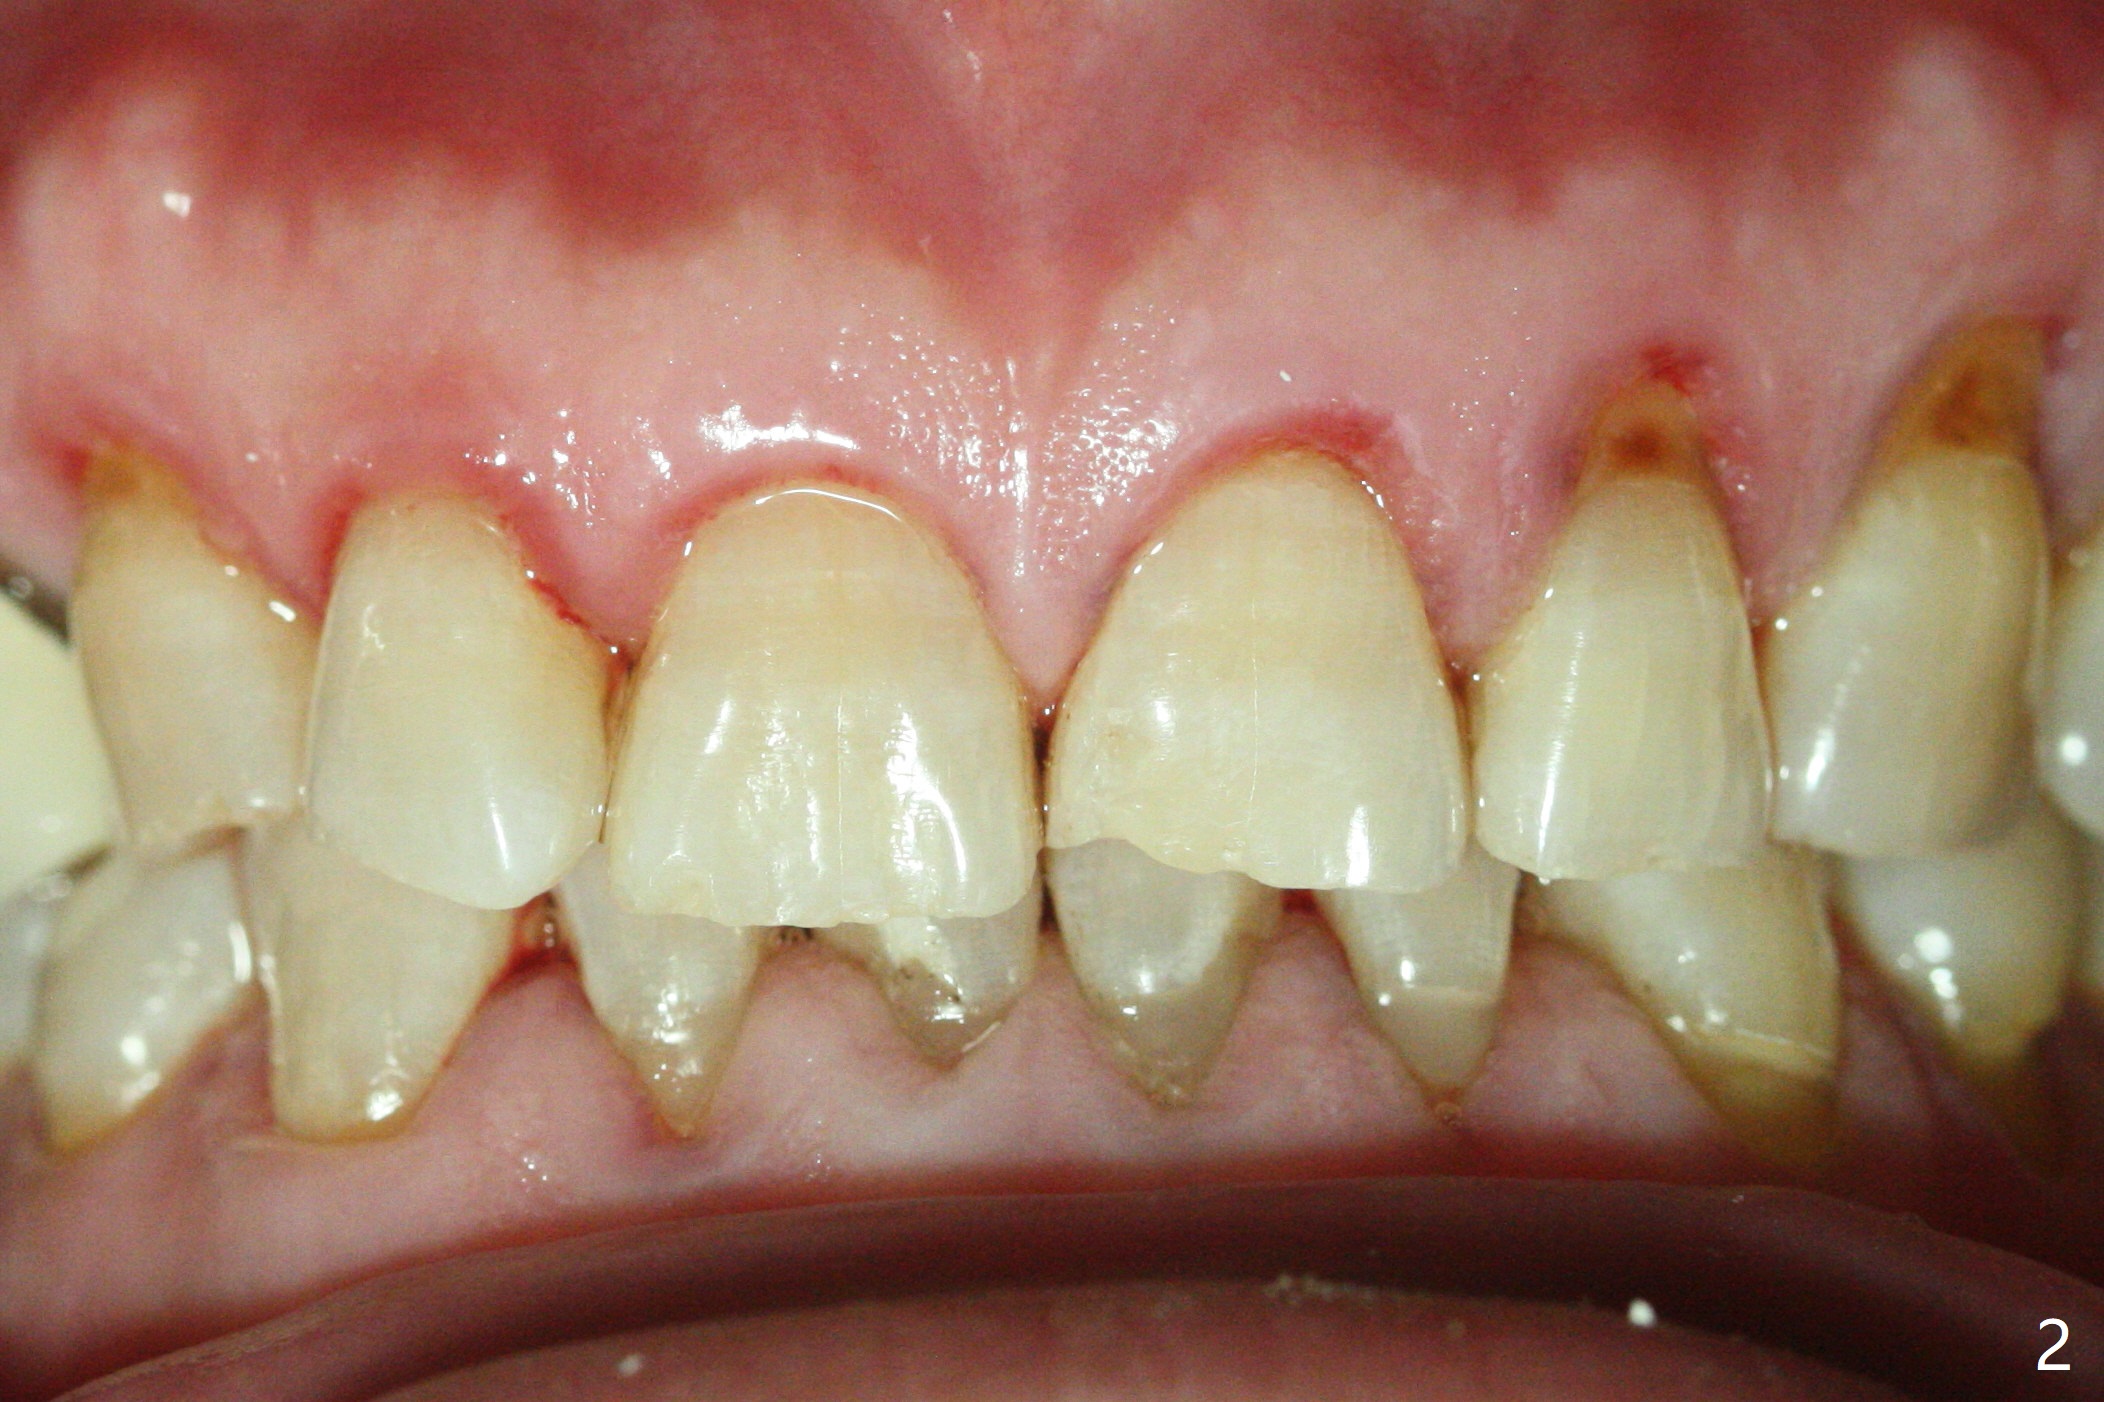

A 54-year-old man returns to office for UL7 upright 6 months post UR5 implant crown cementation (Fig.5,6). The ultimate purpose is to place implants at UL6 and LL 7. The latter will reduce severe occlusal wear especially in the lower anterior teeth (Fig.3,4). To solve the diastema between UR3 and 4 (Fig.1), the bracket at UR3 is placed in the height of contour (Fig.1 insert, Fig.4). Arch wire sequence may automatically close the diastema (Fig.1 insert arrows). In addition to tilting of UL7 (Fig.7), there are diastemata between U1s and UL3 and 4 (Fig.8,9 arrowheads). The patient is not tolerating orthodontic treatment well and requesting finishing the treatment early. We are considering mesializing UL7 instead of upright by placing a mini-implant between UL4 and 5 (Fig.10). There will be less interference of the roots of UL7 with the crown of the impacted UL8. There appears more space for a 1.6x8 mm mini-implant between UL4 and 5 (Fig.11) and UL 3 and 4 (Fig.12). Finally a mini implant is placed distal to UL7.